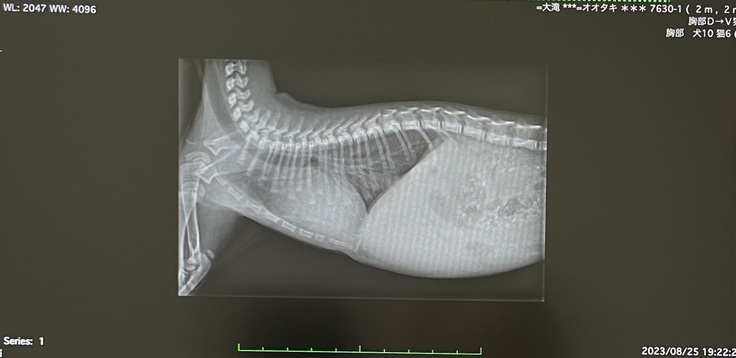

このとき病院で撮ってもらったレントゲンです。

心臓が普通の子猫よりもかなり大きく、肺部分が真っ白(水が溜まっている状態)になっていました…

(心臓が大きく肺のスペースが小さいので、呼吸数が早いそうです。)